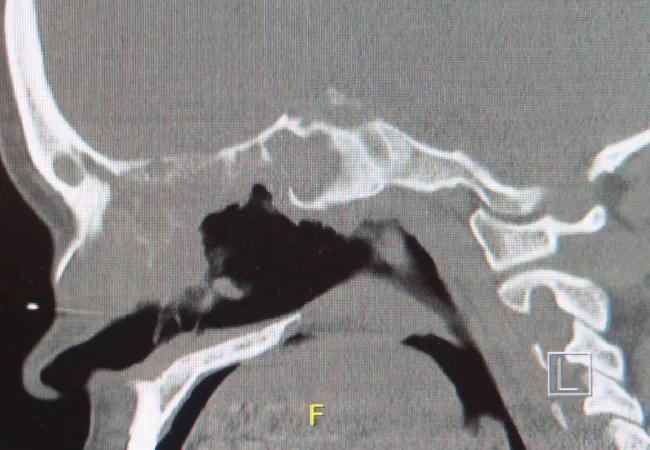

Figure 1. Computed tomography axial view showing loss of the nasal septum and reactive bony thickening (neo-ossification) of the maxillary sinuses. Figure 2. Computed tomography lateral view showing absence of the nasal septum and evidence of collapse of the external nasal bridge.

Examination and imaging play a valuable but not always definitive role. With active inflammation, the nasal membranes will often have an ulcerated or cobblestoned appearance. Findings on computed tomography can include mucosal thickening, perforations, neo-ossification of the sinuses’ long-standing disease and air-fluid levels that can suggest infection. Mucosal thickening is not in itself indicative of active disease and can persist as a result of scarring.